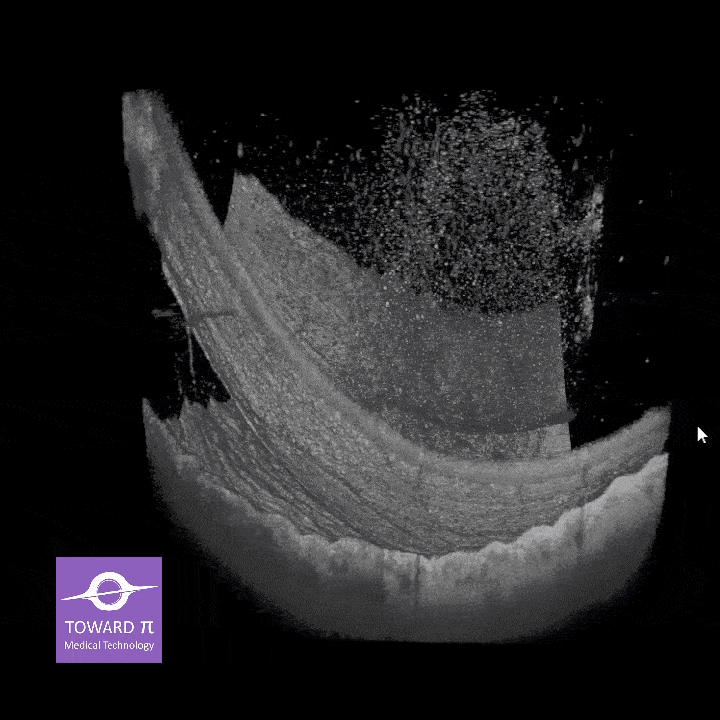

Oba systemy osiągają rozdzielczość osiową ≤ 6 µm oraz ultra-wysoką gęstość wokseli (do 10 mld w BMizar), Pozwalają uwidocznić najdrobniejsze struktury siatkówki, naczyniówki i segmentu przedniego oka.

Oba urządzenia obsługują zarówno OCT, jak i OCTA, oferując algorytmy AI do automatycznej segmentacji warstw, analizę ilościową naczyń oraz 3D-rekonstrukcję. To kompleksowe narzędzia diagnostyczne.

NIEZRÓWNANA JAKOŚĆ OBRAZOWANIA

Pełna diagnostyka

w jednym ujęciu